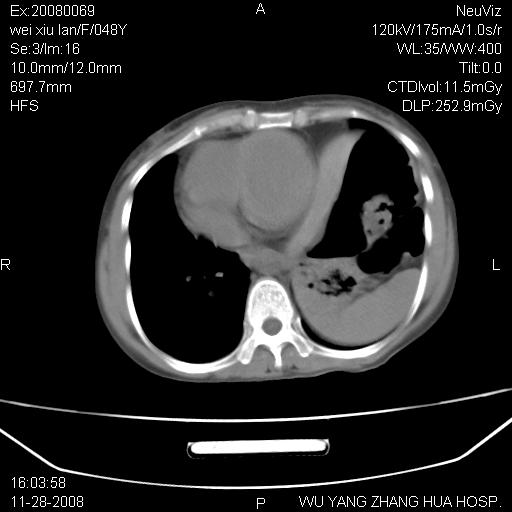

标题: CT16847:女,48岁,咳嗽,发热两日,平常偶有上腹部不适。 [打印本页]

标题: CT16847:女,48岁,咳嗽,发热两日,平常偶有上腹部不适。

胃、脾脏及部分肠管明显升高,并压迫心脏移位,

首先考虑:左侧膈疝。

左侧胸腔内见胃肠及脾脏影

支持膈疝

左膈顶及肋膈角均上移,膈面光滑,考虑左膈肌麻痹